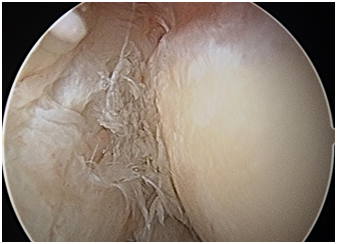

1. Arthroscopic or open65–68 Mini open including Nirschl technique69,70 Long term results of arthroscopic release.71 The arthroscopic release is the commonest form of operative management in our practice (Figures 36).

Figure 6 Arthroscopic tennis elbow release, with visualization and preservation of the LCL.